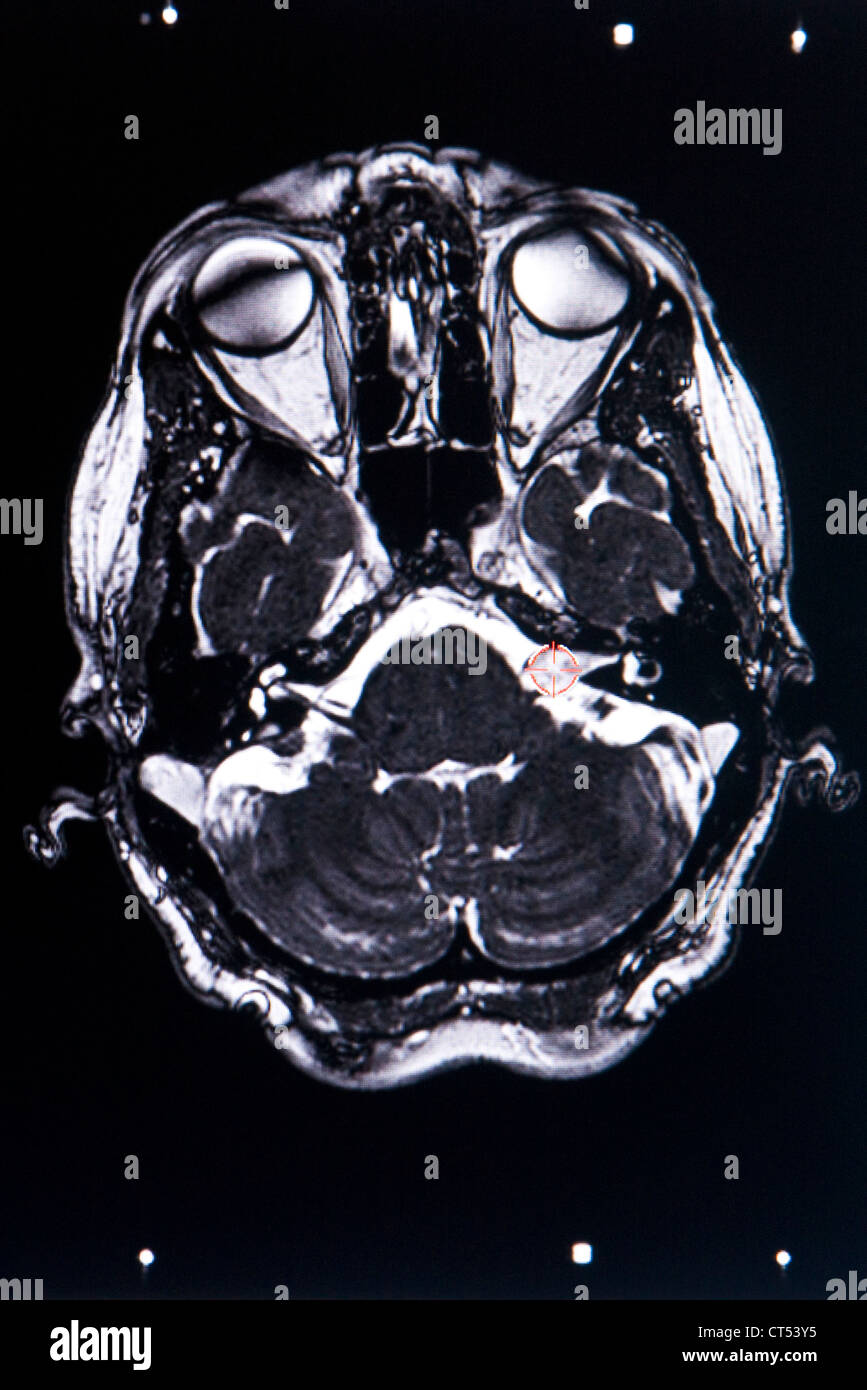

From www.alamy.com

ACOUSTIC NEUROMA, MRI Stock Photo Alamy Acoustic Neuroma And Pain The size and growth rate of the acoustic neuroma. your acoustic neuroma treatment may vary, depending on: acoustic neuromas are noncancerous tumors. These symptoms are due to. They grow on the nerve that connects the brain and ear. the most common symptom of acoustic neuromas, occurring in 90% of patients, is hearing loss on the side of. Acoustic Neuroma And Pain.